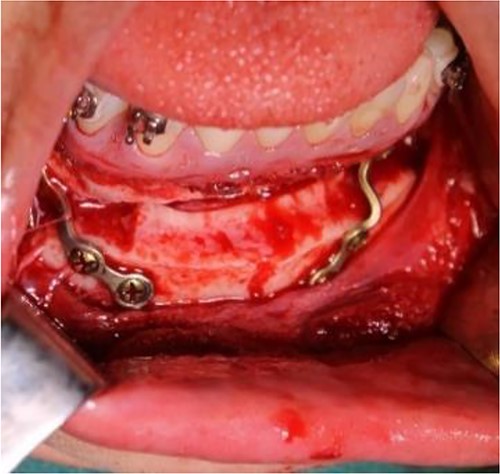

Intraoperative clinical images: positioning and final fixation of the custom prosthesis with screws.